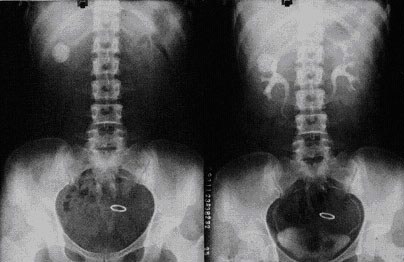

第三是通過X線進(jìn)行腎結(jié)石的檢查。X線檢查腎結(jié)石以及輸尿管結(jié)石檢查的重要方法之一,大約95%以上的尿路結(jié)石都可以通過X線檢查發(fā)現(xiàn)。用排泄性或逆行性腎盂輸尿管造影進(jìn)行輔助便可確定結(jié)石的具體部位、有無梗阻及梗阻程度、對(duì)側(cè)腎功能是否良好、區(qū)別來自尿路以外的鈣化陰影、排除上尿路的其它病變、確定治療方案以及治療后結(jié)石部位、大小及數(shù)目的對(duì)比等。這些數(shù)據(jù)都有重要價(jià)值。